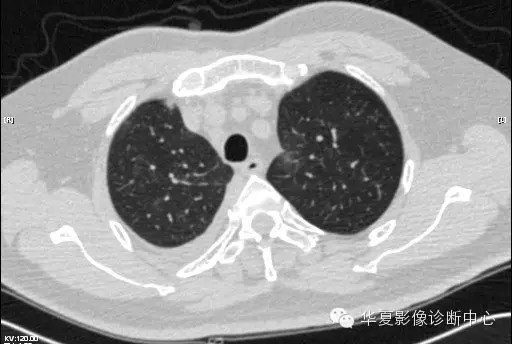

【病例学习】甲型H7N9禽流感一例

男性 63

发热咳嗽5天

2013-4-7CT进一步检查。

最终诊断:H7N9。